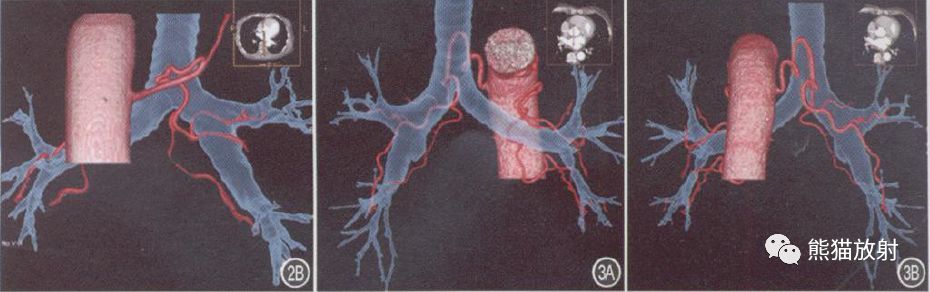

图2A、B 前后位及后前位VR示BA为R1L1, R1源自右侧肋间后动脉, 沿途发出分支呈树枝状分布至右肺各叶,L1源自降主动脉前壁, 发出后即分为2支, 上支沿左主支气管上壁走行, 下支同时行经左主支气管后壁及下壁。

图4A~ C 右肺癌, BA呈R2L1, R1 源自右锁骨下动脉, R2 源自降主动脉前,R1 、R2 均增粗、迂曲, 走行至病灶内, 供血肺癌;L1 起源于降主动脉前壁, 起始处较扭曲, 并分为2支, 均沿左主支气管上壁走行, 分布至左肺上、下叶。